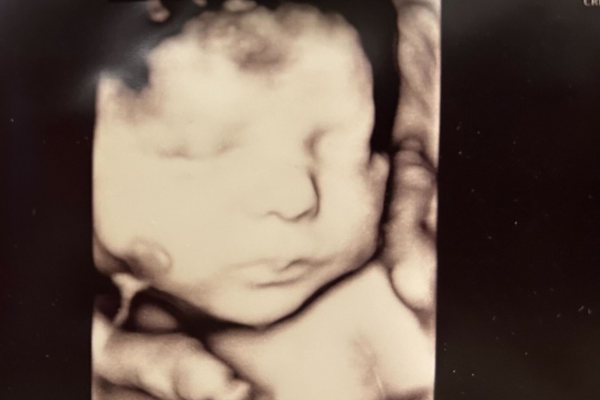

Din baby vejer nu omkring 1800 gram og måler cirka. 40 cm. Alle sanserne udvikles fortsat på højtryk. Du kan opleve, at dit barn puffer igen, hvis du skubber til maven. Det er bare SÅ hyggeligt! Ved en scanning kan man fra dette tidspunkt være heldig at opleve, at barnet har øjenbevægelser. Det er tegn på at barnet også drømmer.

Få en scanning for oplevelsens skyld. Det er det hele værd. Kommende søskende kan virkelig relatere til, at det er et levende barn, der gemmer sig i maven. Se mere her